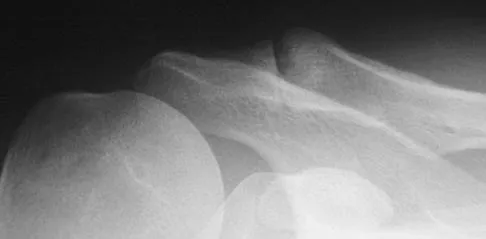

A 14-year-old girl reports hip pain that is exacerbated by weight bearing. A radiograph and biopsy specimen are shown in Figures 16a and 16b. The best course of management should be

Correct Answer: curettage and bone grafting.

The patient has a unicameral bone cyst. Because the subtrochanteric part of the femur is a high-stress region, the treatment of choice is bone curettage and grafting. Azouz EM, Karamitsos C, Reed MH, Baker L, Kozlowski K, Hoeffel JC: Types and complications of femoral neck fractures in children. Pediatr Radiol 1993;23:415-420.